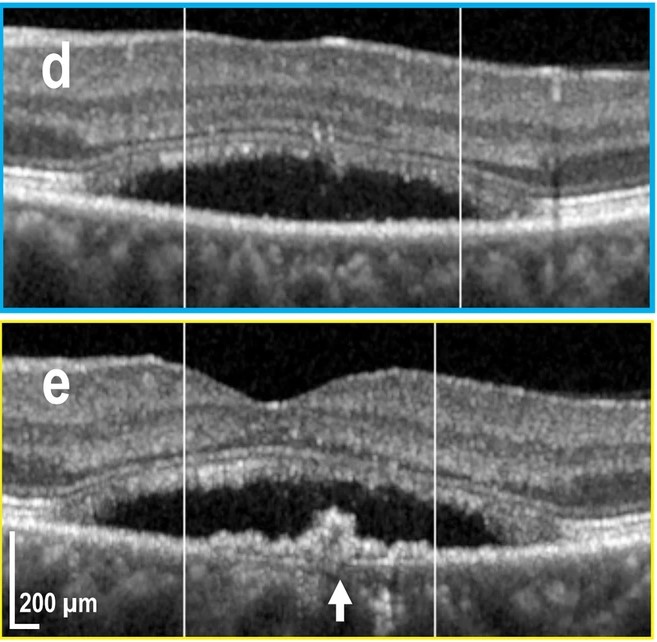

|

Kowalczuk L., Dornier R., Navarro A., Jeunet F., Moser C., Behar-Cohen F., Mantel I., Adaptive Optics-Transscleral Flood Illumination Imaging of Retinal Pigment Epithelium in Dry Age-Related Macular Degeneration, Cells (2025), 14(9), 633. doi: 10.3390/cells14090633. |

Govindahari V., Dornier R., Ferdowsi S., Moser C., Mantel I., Behar-Cohen F., Kowalczuk L., High-Resolution Adaptive Optics-Trans-scleral Flood Illumination (AO-TFI) Imaging of Retinal Pigment Epithelium (RPE) in Central Serous Chorioretinopathy (CSCR), Scientific Reports, 14.1 (2024):13689. doi: 10.1038/s41598-024-64524-4. |

Kowalczuk L., Dornier R., Kunzi M., Iskandar A., Misutkova Z., Gryczka A., Navarro A., Jeunet F., Mantel I., Behar-Cohen F., Laforest T., Moser C., in vivo Retinal Pigment Epithelium Imaging using Transscleral OPtical Imaging in healthy eyes, Ophthalmology Science, 100234 (2022). |

dos Santos F., Laforest T., Künzi M., Kowalczuk L., Behar-Cohen F., and Moser C., Fully automated detection, segmentation, and analysis of in vivo RPE single cells, Eye, June 2020. |

Laforest T., Künzi M., Kowalczuk L., Carpentras D., Behar-Cohen F. and Moser C. , Transscleral optical phase imaging of the human retina, Nature Photonics, March 2020. |